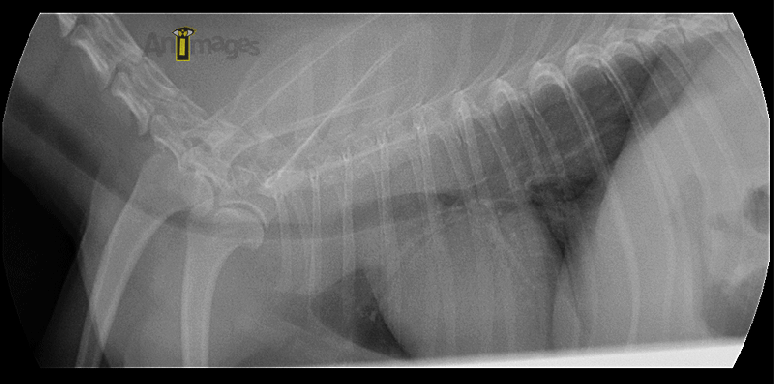

L’examen fluoroscopique effectué après palpation trachéale pour induire de la toux montre hors de tout doute un collapsus sévère affectant non seulement la trachée, mais aussi les bronches principales. L’implication des bronches est importante car elle limite la pose d’une prothèse endoluminale (stent), celui-ci ne pouvant être placé que dans la trachée et jusqu’à environ 1 cm de la carina.

Ces images proviennent de deux instants de la boucle fluoroscopique, illustrant la variation de diamètre important qui a lieu durant la toux chez ce petit chien. Notez le collapsus complete de la trachée (T) thoracique, de la carina et des bronches principales survenant durant cet épisode de toux.